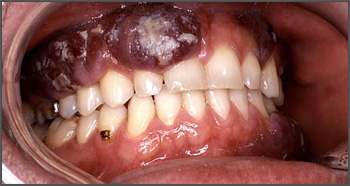

Because the condition can develop anywhere inside your mouth, it can manifest in your jaw as well. Jaw cancer can occur either on the upper jaw, known as the maxilla; or the lower jaw, known as the mandible. If you experience any of the following jaw cancer symptoms, be sure to seek an evaluation by your dentist.

Lumps on the jaw

Lumps on the roof of your mouth or along your gumline may be the only jaw cancer symptoms you experience. These lumps can be a sign that cancer is developing on the jawbone beneath the mouth's soft tissues. If you notice a new lump inside your mouth and it doesn't resolve itself in two weeks, you need to see your dentist.

Swelling of the jaw

Swelling in the jaw is the most common symptom of osteosarcoma as a type of bone tumor that can affect the jaw. This swelling may be visible on the side of your face, but it can also occur inside your mouth. The roof of your mouth may be swollen as well, or you may notice swelling beneath your teeth depending on the location of the tumor. This inflammation is caused by the growth of the tumor inside the bone, and if it leads to gum irritation, your dentist may recommend using a toothbrush with extra-soft bristles.